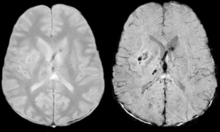

Stroke and hemorrhage

Diffusion weighted imaging offers a powerful means to detect acute stroke. Although it is well known that gradient echo imaging can detect hemorrhage, it is best detected with SWI. In the example shown here, the gradient echo image shows the region of likely cytotoxic edema whereas the SW image shows the likely localization of the stroke and the vascular territory affected (data acquired at 1.5 T).

The bright region in the gradient echo weighted image shows the area affected in this acute stroke example. The arrows in the SWI image may show the tissue at risk that has been affected by the stroke (A, B, C) and the location of the stroke itself (D). The reason that we are able to see the affected vascular territory could be because there is a reduced level of oxygen saturation in this tissue, suggesting that the flow to this region of the brain could be reduced post stroke. Another possible explanation is that there is an increase in local venous blood volume. In either case, this image suggests that the tissue associated with this vascular territory could be tissue at risk. Future stroke research will involve comparisons of perfusion weighted imaging and SWI to learn more about local flow and oxygen saturation.